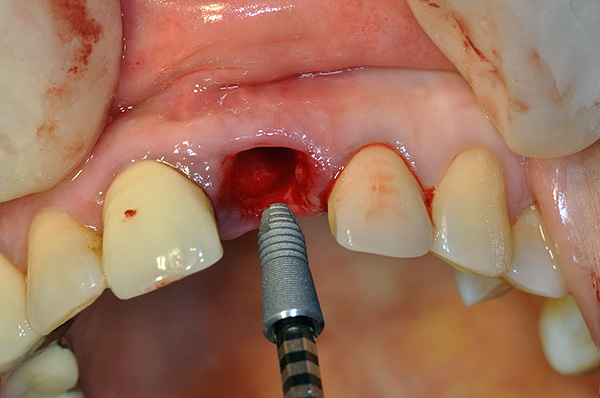

L'operazione per installare l'impianto stesso non richiede più di un'ora e viene eseguita come segue: la gomma viene tagliata, il suo piccolo lembo viene rimosso, il che consente l'accesso al tessuto osseo. Con l'aiuto di frese e frese speciali, si forma un buco nell'osso - il letto sotto l'impianto. Quindi l'impianto viene avvitato nell'osso (come una vite autofilettante) e chiuso con un tappo. Il lembo gengivale ritorna al suo posto ed è suturato - vengono applicate suture.

Il primo metodo di impianto rapido è l'impianto simultaneo. Viene eseguito contemporaneamente all'estrazione del dente (mentre l'approccio classico implica un lungo recupero e guarigione dell'osso dopo tale procedura). Con una tecnica a uno stadio, l'impianto viene installato in un nuovo foro (sfortunatamente, questo non è sempre possibile, soprattutto sullo sfondo dei processi infiammatori, quando il dente deve essere rimosso urgentemente). Con questo approccio, il processo di trattamento è ridotto di uno stadio, il che significa risparmiare tempo e denaro.